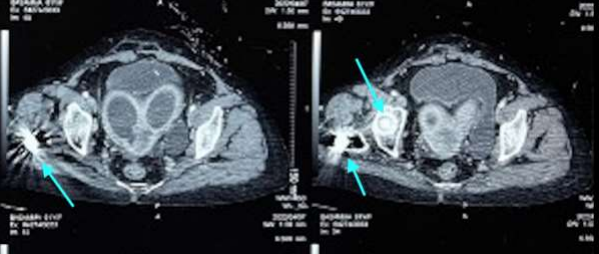

A 63-year-old, fit (ECOG 1) postmenopausal lady, G4P4A0, presented with postmenopausal bleeding with concurrent white discharge per vagina for four months and a history of lower abdominal pain for three months. She underwent surgery with internal fixation for a fracture of the right neck of her femur four years ago. She had no history suggestive of any co-morbidities. Clinically, there was an infiltrative lesion of size 3 x 3.5cm, destroying most of the cervix involving all the fornices and upper 1-1.5cm of the left lateral and posterior vaginal wall. The left parametrium was medially involved with the disease. A biopsy confirmed malignancy, and the histology was squamous cell carcinoma. Local imaging revealed left HUN, making the final diagnosis of IIIB, apart from the bicornuate uterus (Figure 1), with hydrometra in both cornua. The intramedullary nail (Figure 2) was a contraindication for MRI. Her family history was negative for miscarriages.

Figure 1: CT sections show a bicornuate uterus with hydro/pyo metra. The artefacts in the right proximal femur are due to the intramedullary implant.

Figure 2: The implant (in the head, neck & proximal femur) is highlighted with cyan arrows.